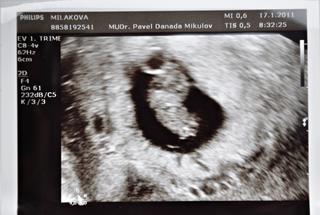

Ahoj holčinky! U doktora jsem dopadla dobře, jsem dnes 7tt+0 a máme SRDÍČKO!!!!! 😵 Všechno bylo v pořádku, panu doktorovi se vše líbilo. Dostala jsem pro jistotu utrogenstan na podporu funkce žlutého tělíska, kvůli předchozímu potratu, tak abychom to trochu podpořili. Kontrola za 14 dní - 31.1.2011. Děkuju, že jste držely pěsti!!!! 😵 😵 😵

cajori17......................8 tt, KO 17.1.

Aja............................. 31.12. našla // , 6tt+2